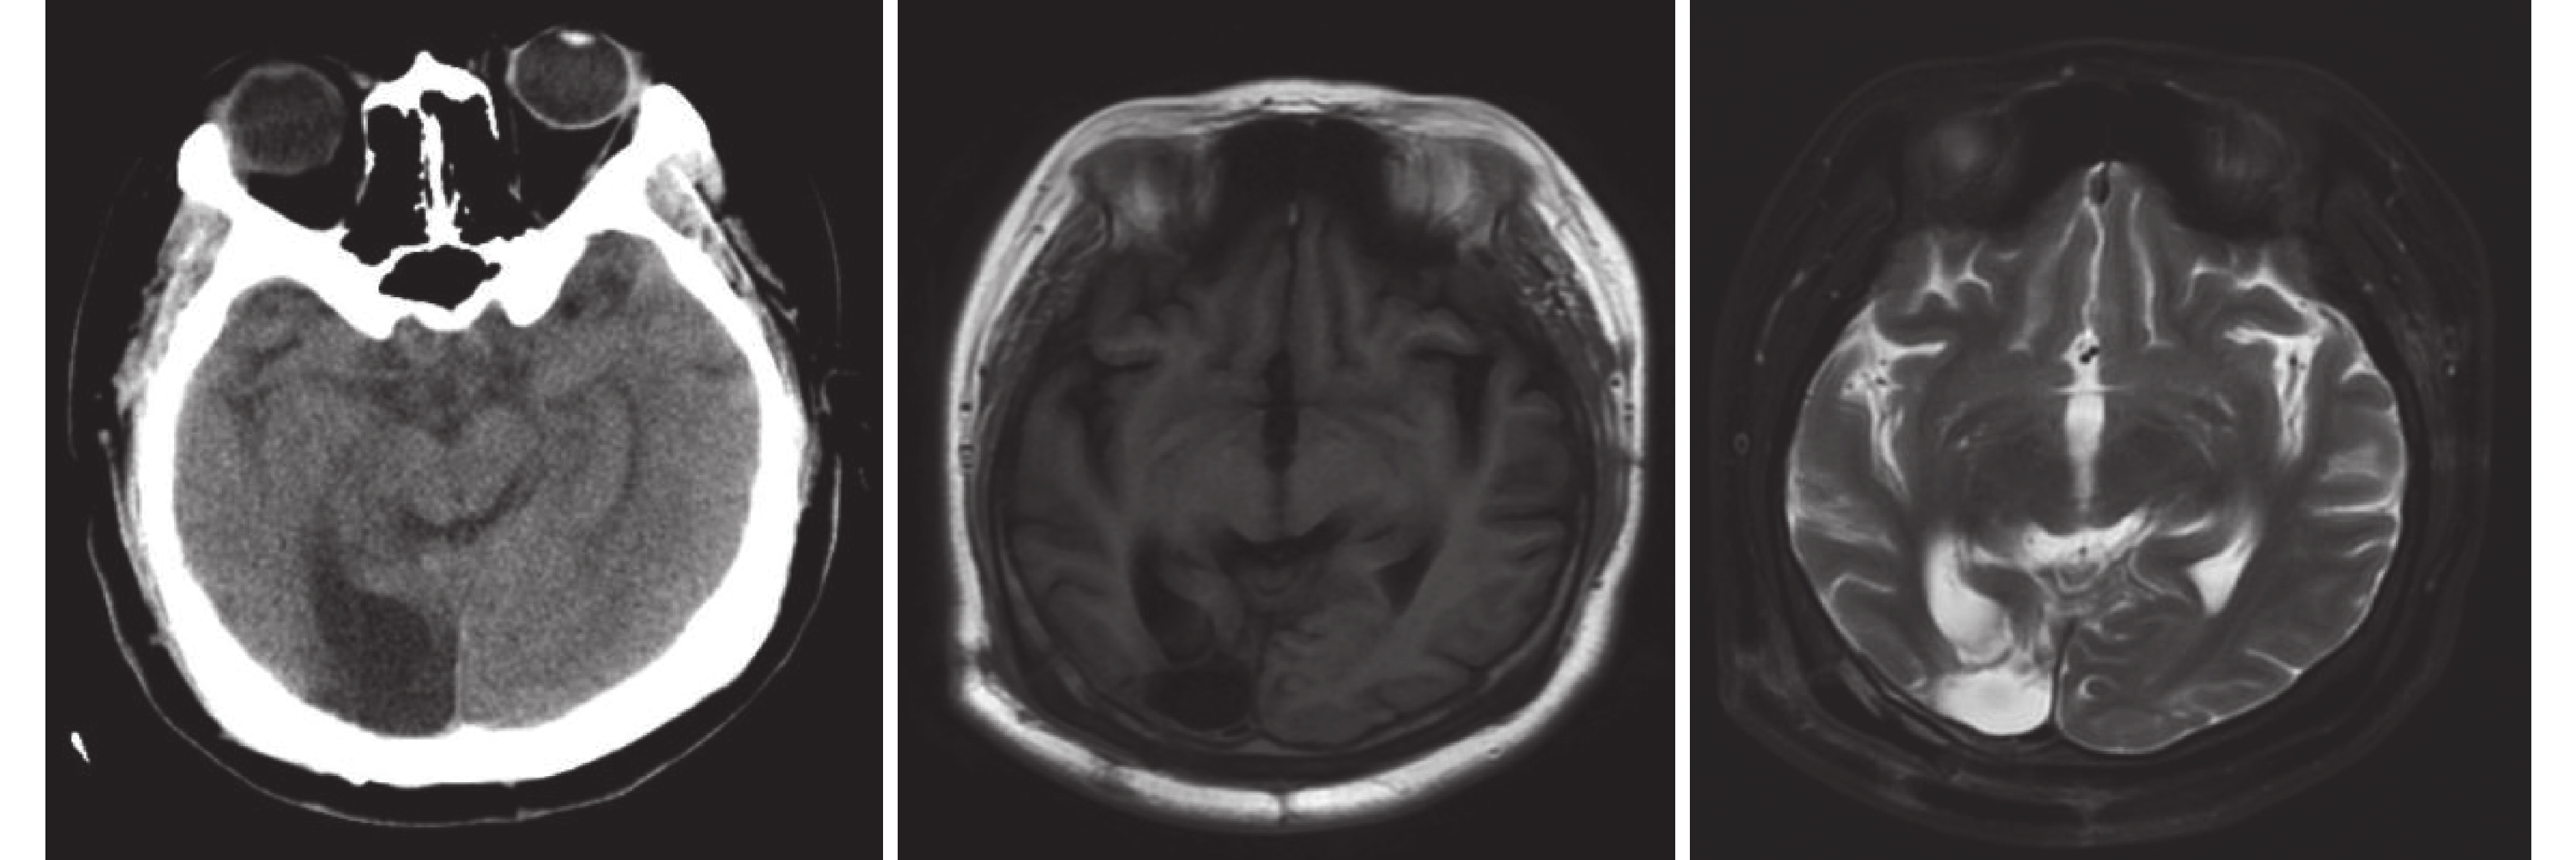

入院查體:神志清晰,精神不佳,對答可。雙瞳孔等大等圓,D=3 mm,光反射存在。左側眼瞼順目較右側少,鼓腮左側漏氣,示齒口角稍右偏。腦膜刺激征陰性。四肢可自主活動,肌力5級,肌張力正常。病理征陰性。視野缺損。入院后查頭部計算機斷層掃描(Computerized tomography,CT)及核磁共振(Magnetic resonance imaging,MRI)提示:雙側枕葉軟化灶。磁共振波譜(Magnetic resonance spectroscopy,MRS)檢查提示:左側海馬代謝較右側低(圖1)。長程視頻腦電圖(Videoelectroencephalography,VEEG)提示:發作間期右側額極、額區、左側額極、額區、顳區及額中線少量不同步中低波幅尖波散發出現,左枕區及后顳區可見部分低波幅尖波;視頻腦電圖監測發作期表現為愣神-咂嘴-右手摸索動作,持續約30 s后出現咳嗽,意識逐步好轉,但此時意識尚未完全恢復清楚,此后患者自行摘除網帽,事后不自知。發作期視頻腦電圖表現為剛開始在右枕(O2)、右后顳區(T6)出現低波幅快節律改變,波幅壓低,其后雙側額顳區出現高波幅慢波節律(圖2)。